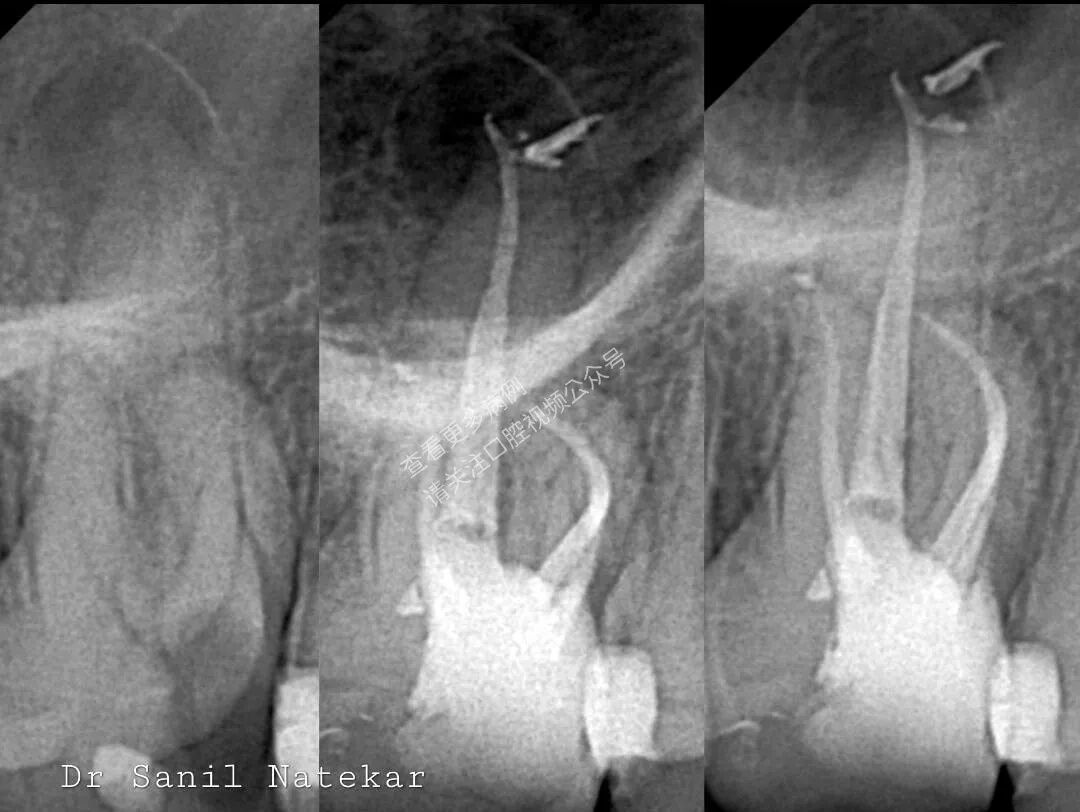

在根管治疗中,MB2根管(近中颊侧第二根管)的遗漏仍是持久难题。更复杂的是,当MB2在根中部(mid-root level)时,常规器械难以顺利进入与成形,显著增加治疗失败风险。

选用合适冶金特性的镍钛器械(如热处理M-wire、CM Wire或Blue/ Gold合金),以提升柔韧性与抗疲劳性,有效应对弯曲解剖。

传统定位法(如DB-P线法或MB-P垂线法)常仅提供一个区域范围,而非精确点位。Dr. Wang提出一种联合几何定位法,显著提高可预测性:

定位原理:MB2的预测位置 =① 过MB点作一条平行于DB–P连线的直线与② 从DB点向MB–P连线所作垂线的交点。

该方法通过融合两种经典技术的优势,克服了单一方法仅能界定“可能区域”的局限,实现更精准的点位预测。